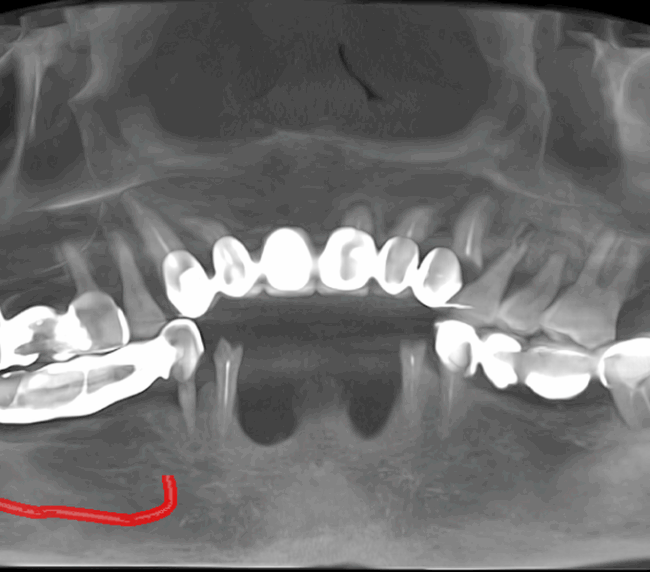

Tomografie (CBCT)

Caz 2